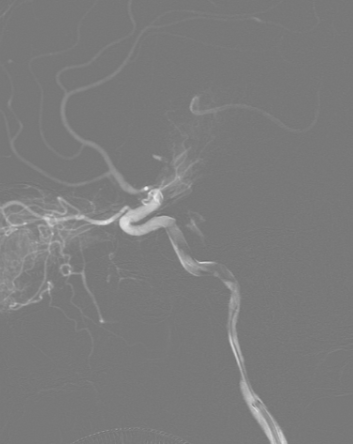

在泥鳅导丝及5F MPA1造影管配合下将6F股动脉长鞘至于左侧颈总动脉行路图,在200cm Sur-reach®微导丝配合下将2.5*15mm颅内球囊扩张导管扩张后,将6F导管鞘通过颈内动脉起始部闭塞段,行路图可见颈内动脉颈段至海绵窦段后膝处血栓影,左侧大脑中动脉闭塞。

将6F Oneering®远端通路导管自颈段负压抽吸至左侧大脑中动脉M1段,抽吸出大量血栓。行路图提示颈内动脉及大脑中动脉通畅。

术后造影:可见左侧颈内动脉通畅,大脑前动脉不显影,因患者前交通动脉开放,未处理。